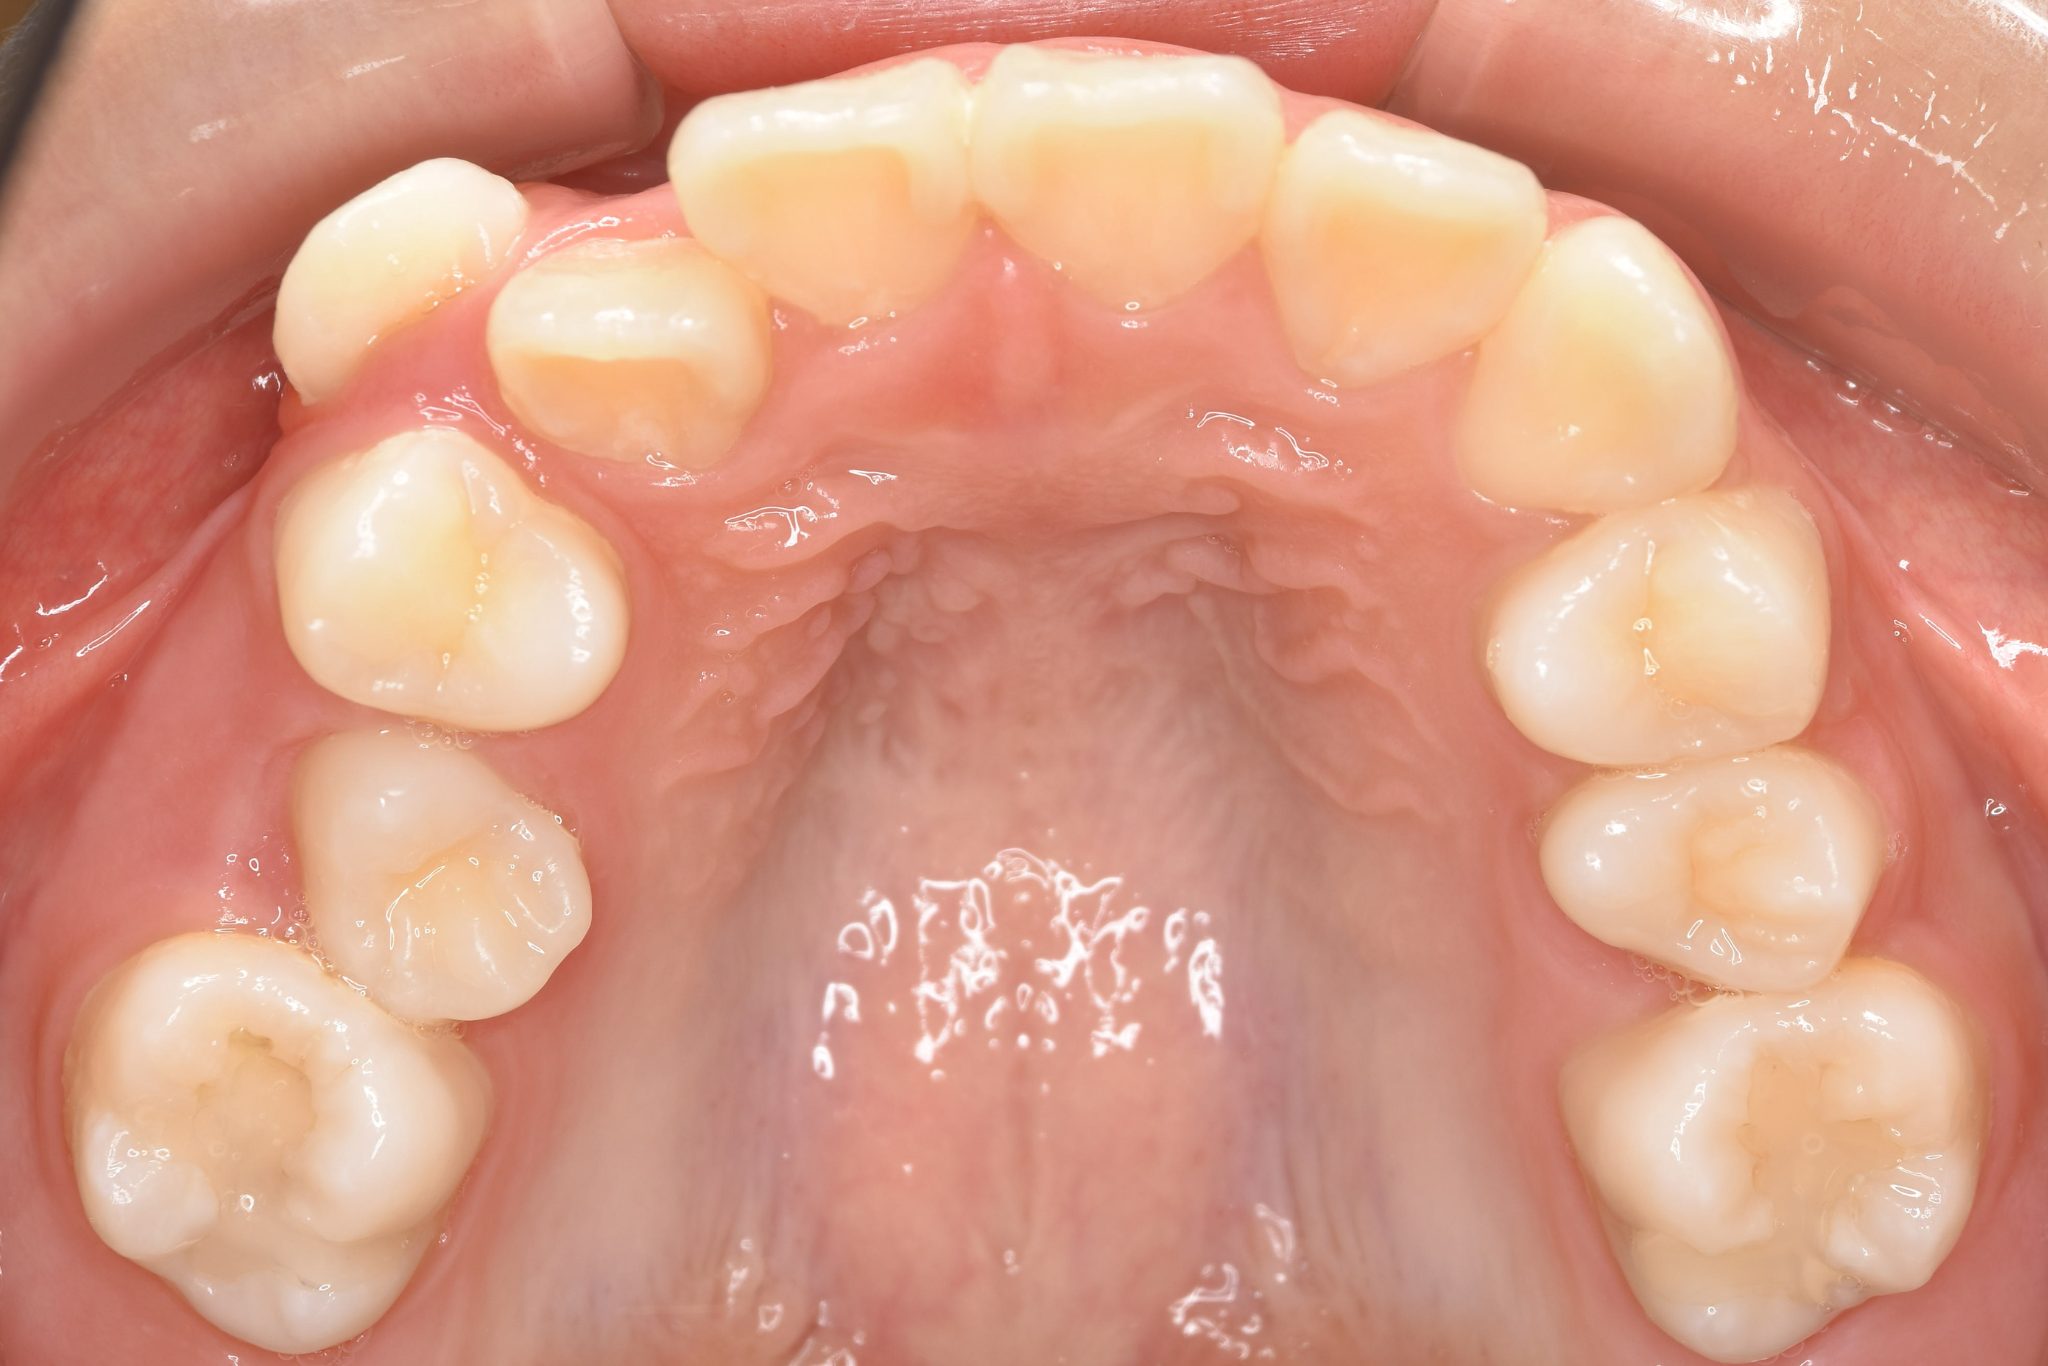

ビフォー

ワイヤー矯正治療|症例_1324

主訴 下顎が出ている

施術内容 MSEと下顎リンガルアーチを用いて上下顎骨を拡大した。

その後マルチブラケット装置を用いて非抜歯で歯牙を配列し、良好な咬合を獲得した。